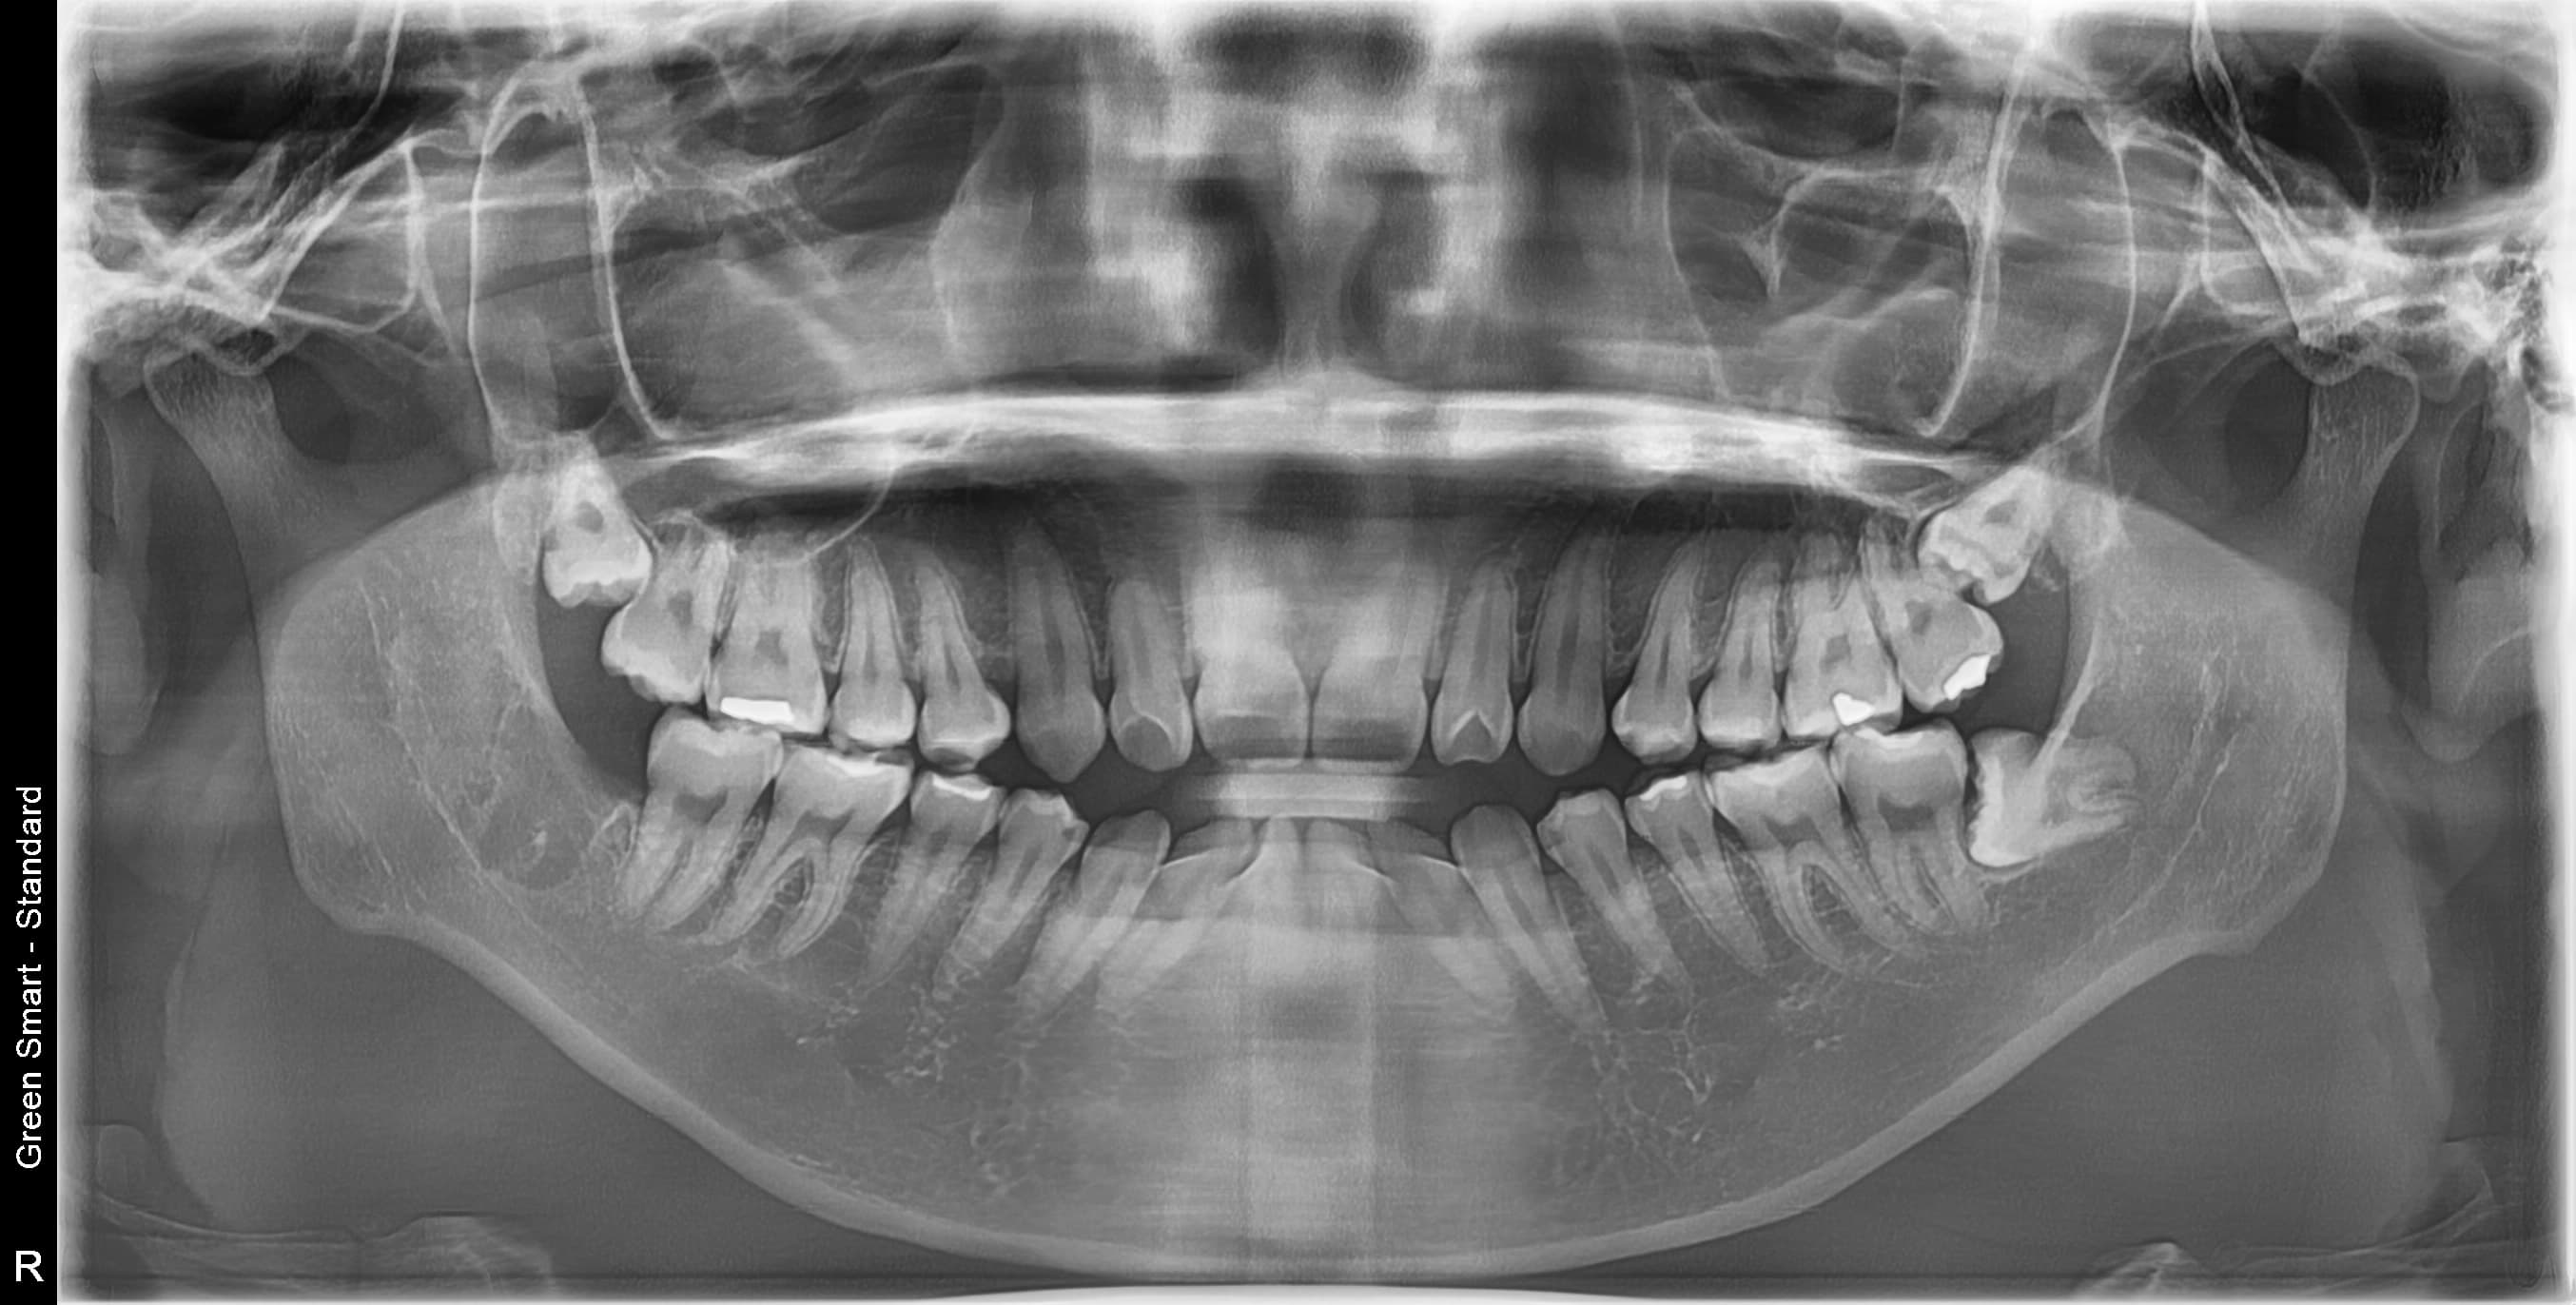

저위험

정상 사랑니

정상적으로 자란 사랑니도 관리가 어려워 충치 위험이 높습니다

중위험

부분매복 사랑니

음식물이 끼기 쉽고 염증이 자주 발생합니다

고위험

완전매복 사랑니

낭종 형성 가능성이 있어 조기 발치가 필요합니다

치근만곡 사랑니

뿌리가 구부러져 있어 발치 난이도가 높습니다

즉시 처치 필요

수평매복 사랑니

앞 치아를 밀어 치열 불균형과 충치를 유발합니다